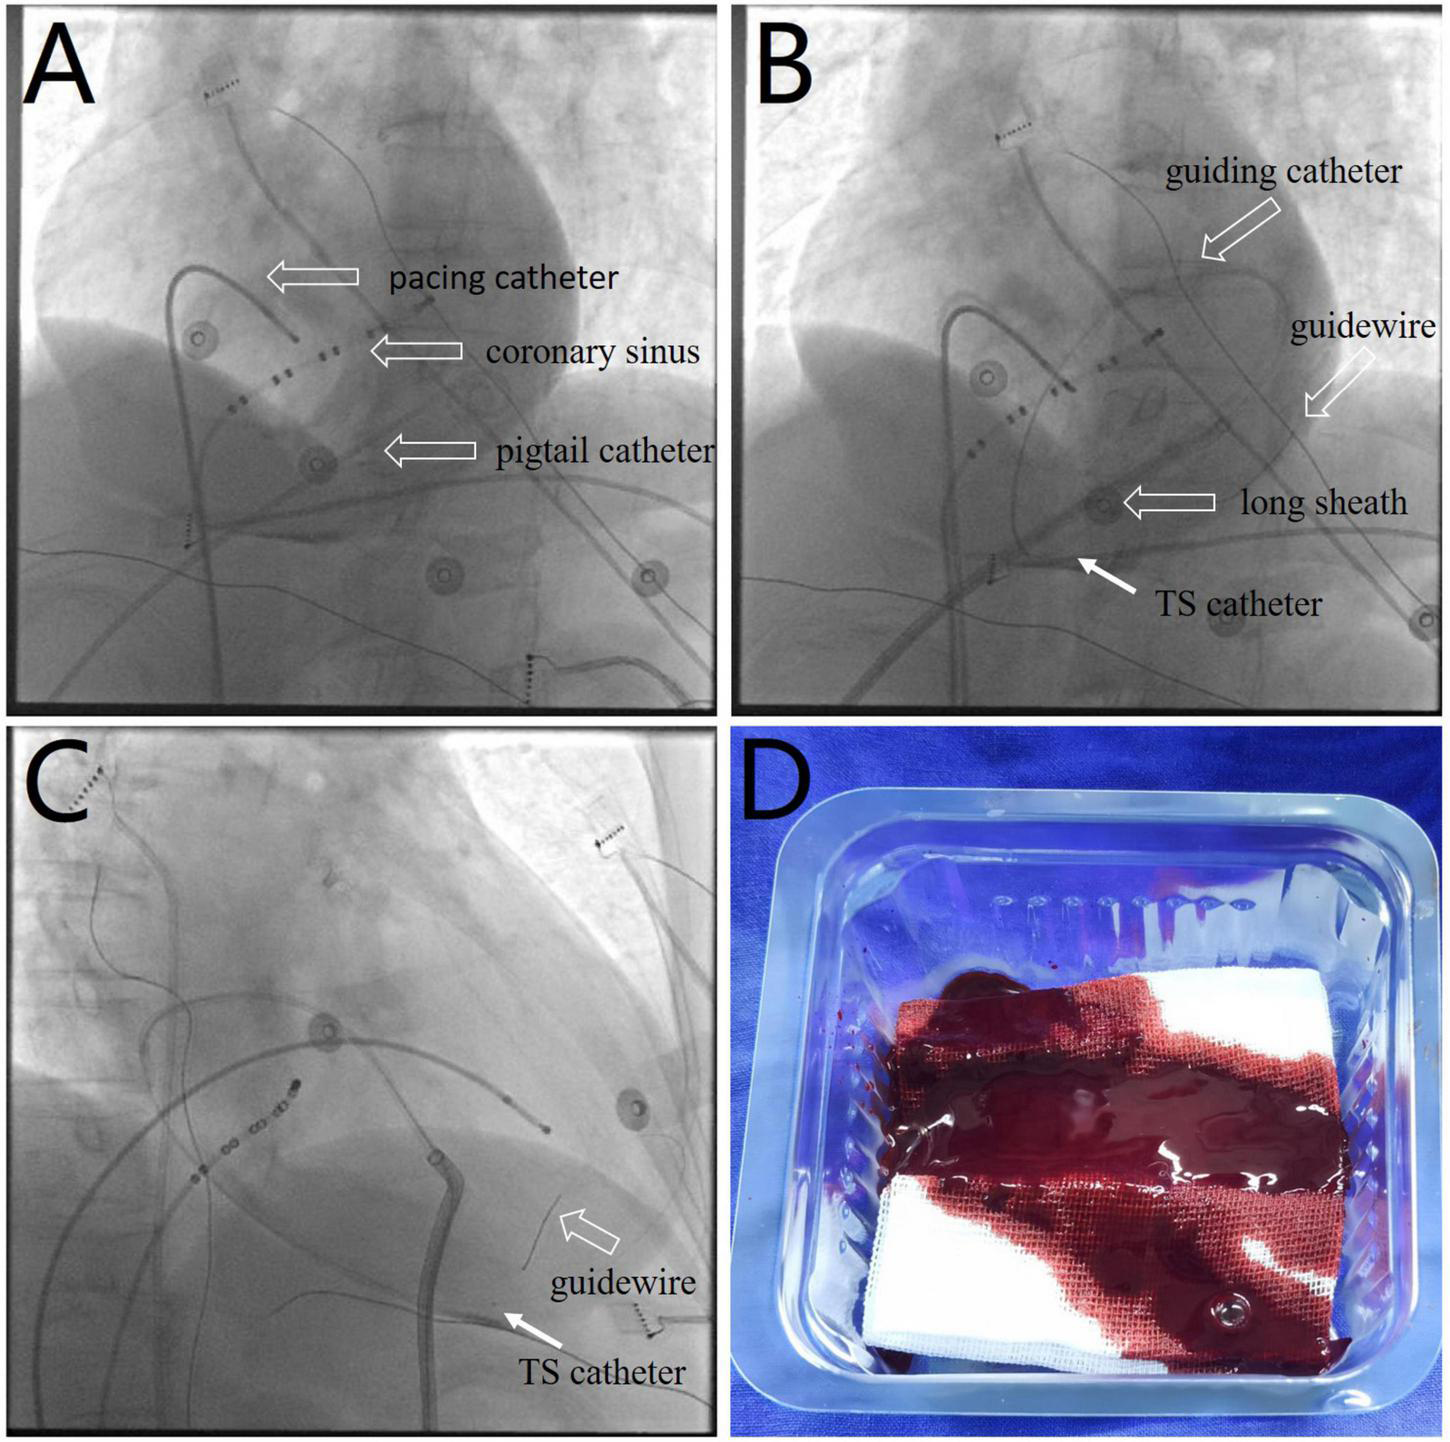

FIGURE 2

(A) Fluoroscopic image showing a near-normal sized cardiac silhouette (Supplementary Video 5), although the patient’s blood pressure decreased to 90/62 mmHg. (B,C) Images showing the use of a thrombus aspiration catheter (white arrows) for thrombus aspiration from multiple pericardial sites with cautious manipulation of the guiding catheter and guidewire (Supplementary Videos 6, 7). (D) Image showing a sludge-like appearance of blood (as opposed to a formed thrombus) drained by the aspiration catheter. TS, thrombus aspiration.

The patient’s blood pressure was temporarily stable at approximately 90/60 mmHg; therefore, intrapericardial thrombus aspiration was attempted before surgery. However, thrombus aspiration failed using a pigtail catheter, which was replaced by an 8.5 F long sheath (SL1, Abbott, MN, United States). Unfortunately, thrombus aspiration through the sheath was also unsuccessful. Thereafter, we used a dedicated thrombus aspiration catheter. A 6F guiding catheter (Judkins R4.0, Medtronic, MN, United States) was inserted through the long sheath into the pericardial cavity via an angioplasty guidewire (BMW, 0.036 cm × 190 cm, Abbott, MN, United States), and a thrombus aspiration catheter (Thrombuster II, Kaneka Medical Products, Osaka, Japan) was advanced into the pericardial cavity via the guidewire. Following manipulation of the guiding catheter and guidewire, we could maneuver the thrombus aspiration catheter to successfully aspirate the thrombus from multiple sites across the pericardium (Figures 2B,C and Supplementary Videos 6, 7). Sludge-like blood (instead of a thrombus) was drained using the aspiration catheter (Figure 2D). We aspirated 120 ml of sludge-like blood after 10 min. The patient was hemodynamically stable, and blood pressure returned to 123/62 mmHg. Echocardiography revealed mild effusion and a round hyperechoic thrombus (2.5 cm × 1.7 cm) in the vicinity of the right ventricular apex (Figure 3B). A pigtail catheter was placed to monitor the pericardium, and the patient was transferred back to the ward.